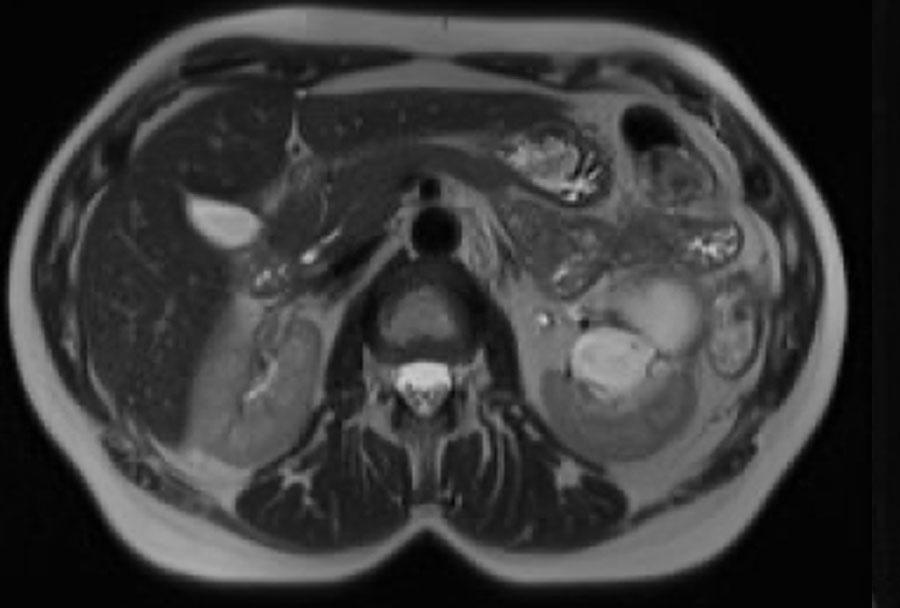

Có một khối dạng nang ở thận trái với nhiều vách ngăn mỏng ngấm thuốc.

Tổn thương được phân loại là Bosniak IIF.